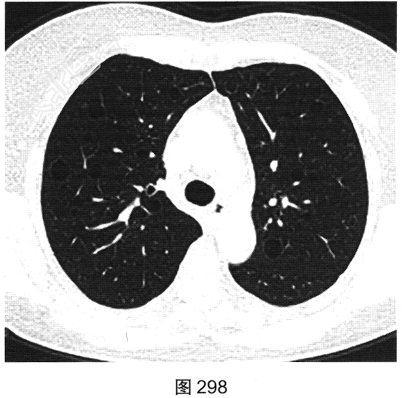

- 多项选择题3.[提示]HRCT图像如图298~图301所示。从患者的HRCT图像中可见哪些阳性征象( )

A、双侧腋窝及纵隔内多发增大淋巴结

B、双肺多发薄壁透亮影

C、小叶间隔增厚

D、右肺多发钙化结节灶

E、双肺多发磨玻璃样密度影

F、支气管扩张